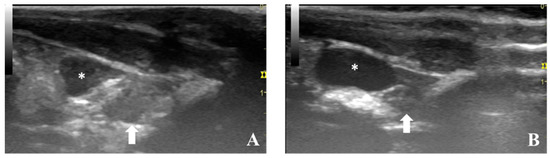

5.1. Ultrasonography